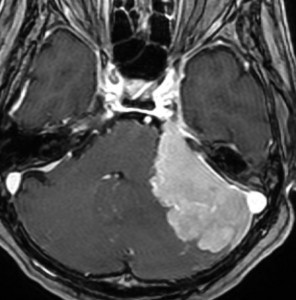

microcystic meningioma 微小のう胞性髄膜腫

数年間経過観察されゆっくり増大したものです。多房性腫瘍です。

多くののう胞を含む髄膜腫です。実質部分では類円形の腫大核を有し核小体が明瞭な細胞がシート状に増生しています。細胞密度が高い部分がありますが,MIB-1染色率は2%程度です。WHO grade 1 microcystic meningiomaの像です。